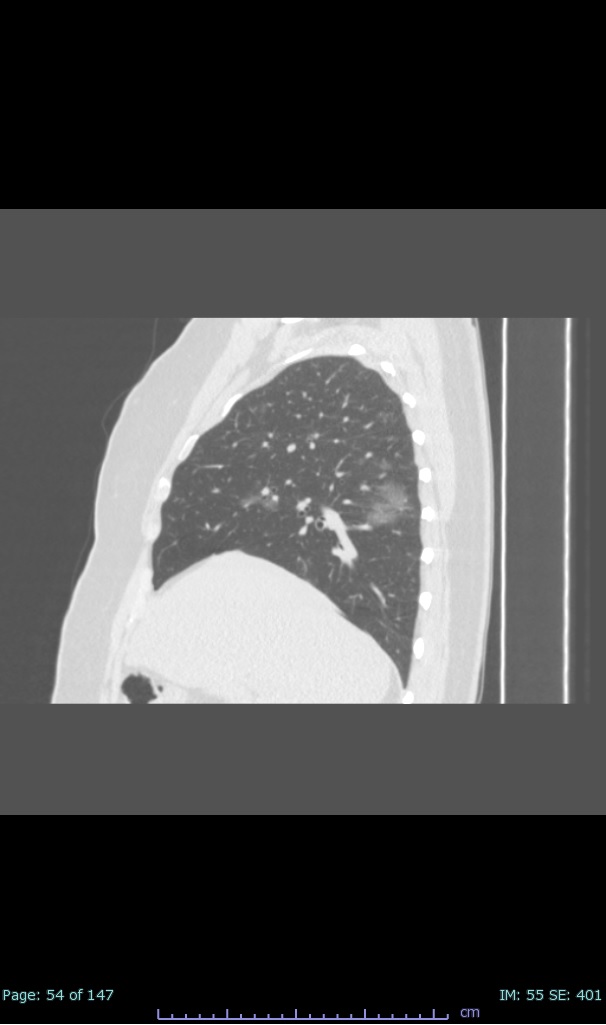

- 100% subpleural involvement, 33% + centrolobular involvement

- 40% even apical/basilar, 27% basilar dom, 5% mid dom. 1/17

- 66% had some + CXR finding I could correlate to a CT finding